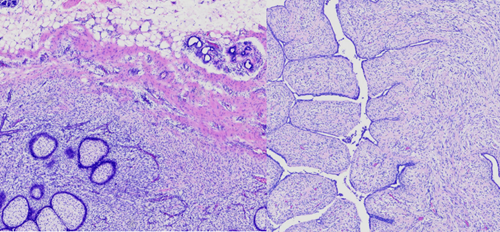

叶状肿瘤在显微镜下具有特征性的“叶状”结构,由活跃增生的间质细胞和受挤压的导管共同构成。根据细胞形态、生长活跃度、边界情况等多项病理指标,可将其分为良性、交界性和恶性三种类型。病理诊断分级5要素:①间质细胞异型性、②间质是否过度生长、③核分裂像、④细胞的丰富程度、⑤肿瘤边界情况。这种分级对于后续治疗和随访方案的制定至关重要。

1.良性叶状肿瘤:间质细胞异型性小,无过度生长,核分裂少见,轻度增生,导管周细胞增生见“袖套”样结构,边界清晰。良性占大多数,类似纤维腺瘤,手术完整扩大切除后预后良好。

(图:良性叶状肿瘤,可见叶状结构及“袖套”样排列)